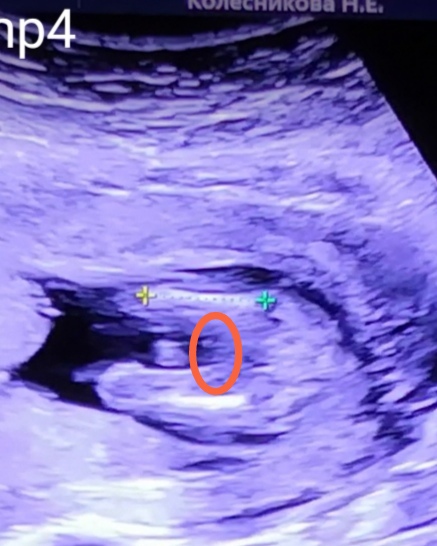

Мария Солнце

Я надеюсь, что это все-таки мальчик. Я тоже думала, что здесь половые губы, хоть и сказали сразу, что это Мальчик. Здесь выделила, чтобы ты не всматривалась в фото в сообщении🤗

Мне одна узистка, на ранних сроках сказала, что если разделение сильное - большая вероятность девочки. Вроде я куда нужно смотрю... Девочка у вас